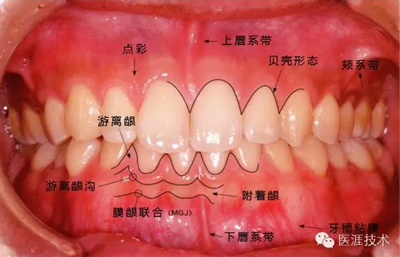

健康、正常的牙周組織如何形成?

健康牙周組織的牙齦邊緣呈珊瑚粉,邊緣牙齦略呈圓弧狀。牙間可見三角形的牙間乳頭,牙齦邊緣相連呈貝殼形。

附著齦與游離齦相連時(shí),有時(shí)有游離齦溝存在(成人的30~40%)。

附著齦通過膠原纖維牢固結(jié)合骨骼與牙骨質(zhì),因此可見不可動、硬而緊繃的點(diǎn)彩(橘皮樣點(diǎn)狀凹凸)。

從牙齦牙槽粘膜到根尖有牙槽粘膜。牙槽粘膜為暗紅色,與骨骼結(jié)合較松,故可動。